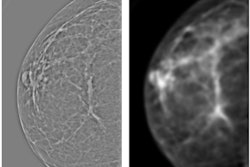

We explore that question in a new article in our Women's Imaging Community. Researchers from Johns Hopkins Hospital wanted to learn more about the effects of new value-based payment models, so they examined mammography screening rates over three years at more than 200 ACOs.

Their findings? They saw a small but statistically significant increase in mammography screening rates over the study period -- increases that were not seen in traditional fee-for-service plans. Learn more by clicking here.